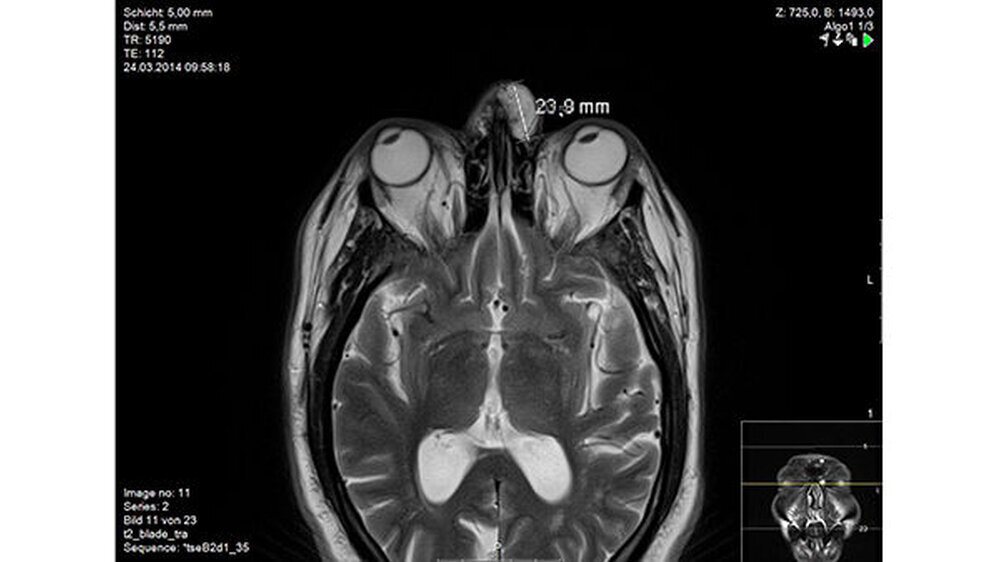

In der Magnetresonanztomografie des Gesichtsschädels zeigte sich eine etwas lobuliert imponierende und signalreiche Läsion frontonasal subkutan links. Der Tumor war mittellinienüberschreitend und zeigte ein koronares Ausmaß von 20 x 40 Millimetern sowie ein transversales Ausmaß bis zu maximal 24 Millimeter (Abbildungen 2 und 3 ).

Es lag ein intensives, jedoch etwas heterogenes Kontrastmittel-Enhancement vor. Die Drainage des Prozesses erfolgte über ein Galeagefäß, die Vena angularis sowie in ein supraorbitales Gefäß links. Ein Nachweis einer angrenzenden Läsion in der Kalotte und Orbita links lag nicht vor.